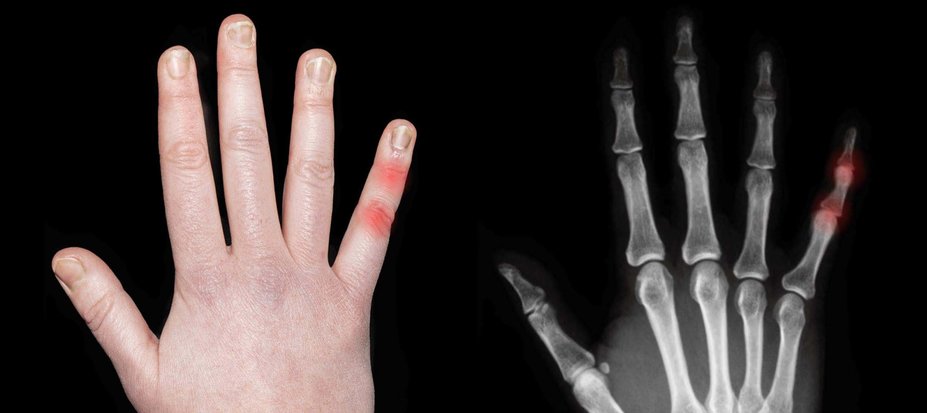

WHAT TO LOOK FOR

RED FLAGS

Nail psoriasis

~3X higher risk3* for developing PsA